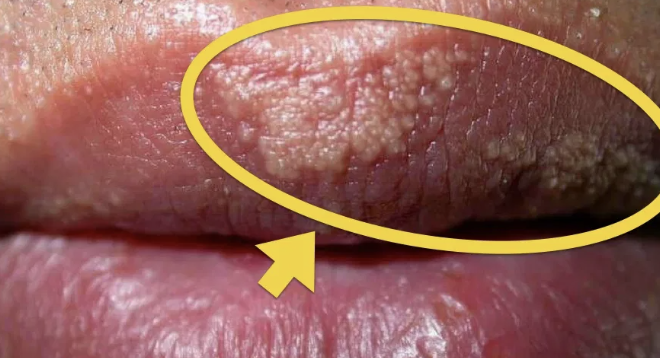

Fordyce Spots

Normal Finding for 3. Buccal Mucosa

Yellowish-whitish raised spots

Normal ectopic sebaceous glands